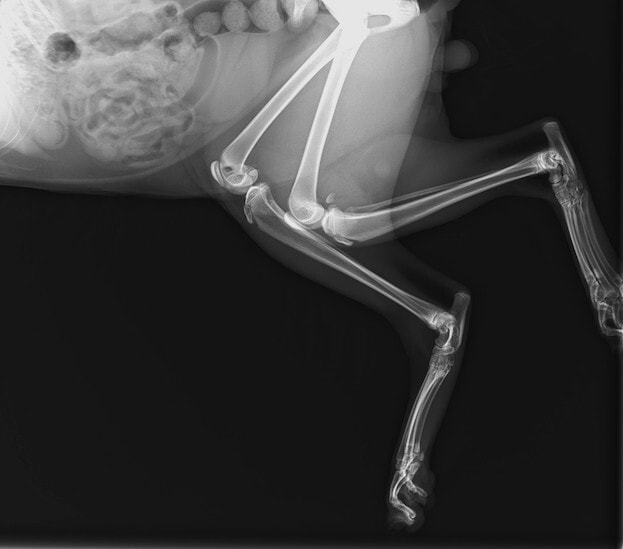

ペルシャ猫 11ヶ月齢 雄

他院にて左大腿骨遠位の成長板骨折(salter-harrisⅠ型)が認められており、治療相談を目的として来院。当院にて、キルシュナーワイヤーを用いたピンニングにより骨折部位の整復を行いました。術後の経過は良好で、現在も経過観察中です。

術前レントゲン